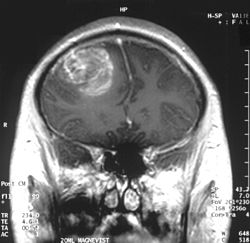

Coronal MRI with contrast of a glioblastoma WHO grade IV in a 15-year-old male.

גידולי המוח הממאירים מסווגים בהתאם לתא המקור ולדרגת ממאירות הגידול על פי דירוג ארגון הבריאות העולמי. GBM הנו הגידול בעל דרגת הממאירות הגבוהה ביותר - דרגה 4 (Grade IV).